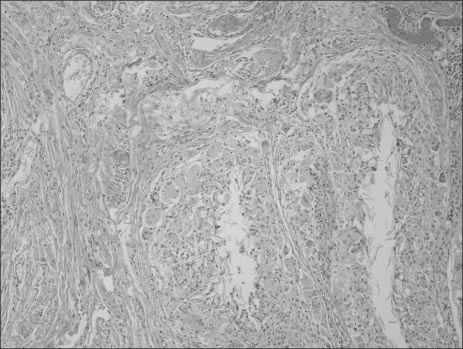

Fig. 4

Histopathologic finding reveals that the unilocular cystic cavity is lined by a stratified squamous epithelium (H&E, ×40).

Fig. 4 Histopathologic finding reveals that the unilocular cystic cavity is lined by a stratified squamous epithelium (H&E, ×40).